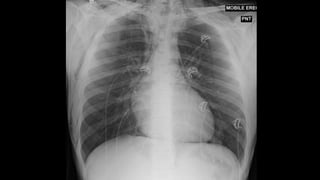

ENFISEMA SUBCUTÂNEO

TRAUMA É CAUSA MAIS COMUM!

SINAL DA FOLHA DE GINGKO